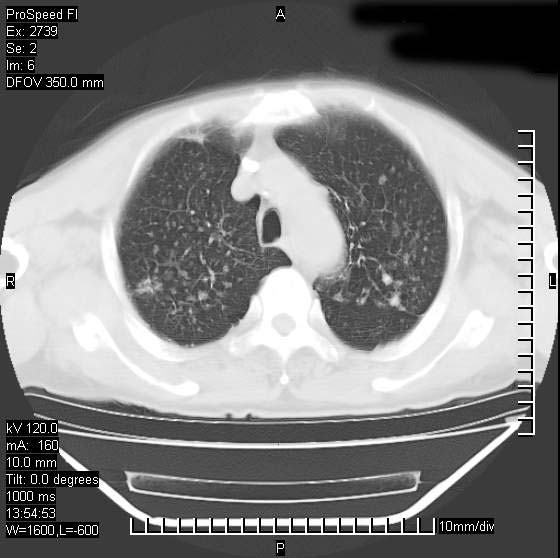

以下是引用andymaomao在2007-12-7 15:54:00的发言:[br]1.双上肺陈旧肺tb灶;[br]2.双中上肺矽肺;[br]3.双肺气肿;[br]4.图中箭头所指乃下腔静脉。

以下是引用山之魂海之韵在2007-12-7 18:59:00的发言:[br]支持矽肺,左肺上叶陈旧性结核,肺气肿。箭头所指乃下腔静脉。下腔静脉显影比主动脉显影迟,增强动脉后迟可以是不均匀的。

以下是引用chengjiaqiu1在2007-12-7 17:49:00的发言:[br]矽肺,左肺上叶陈旧性结核,肺气肿。中箭头所指乃下腔静脉。